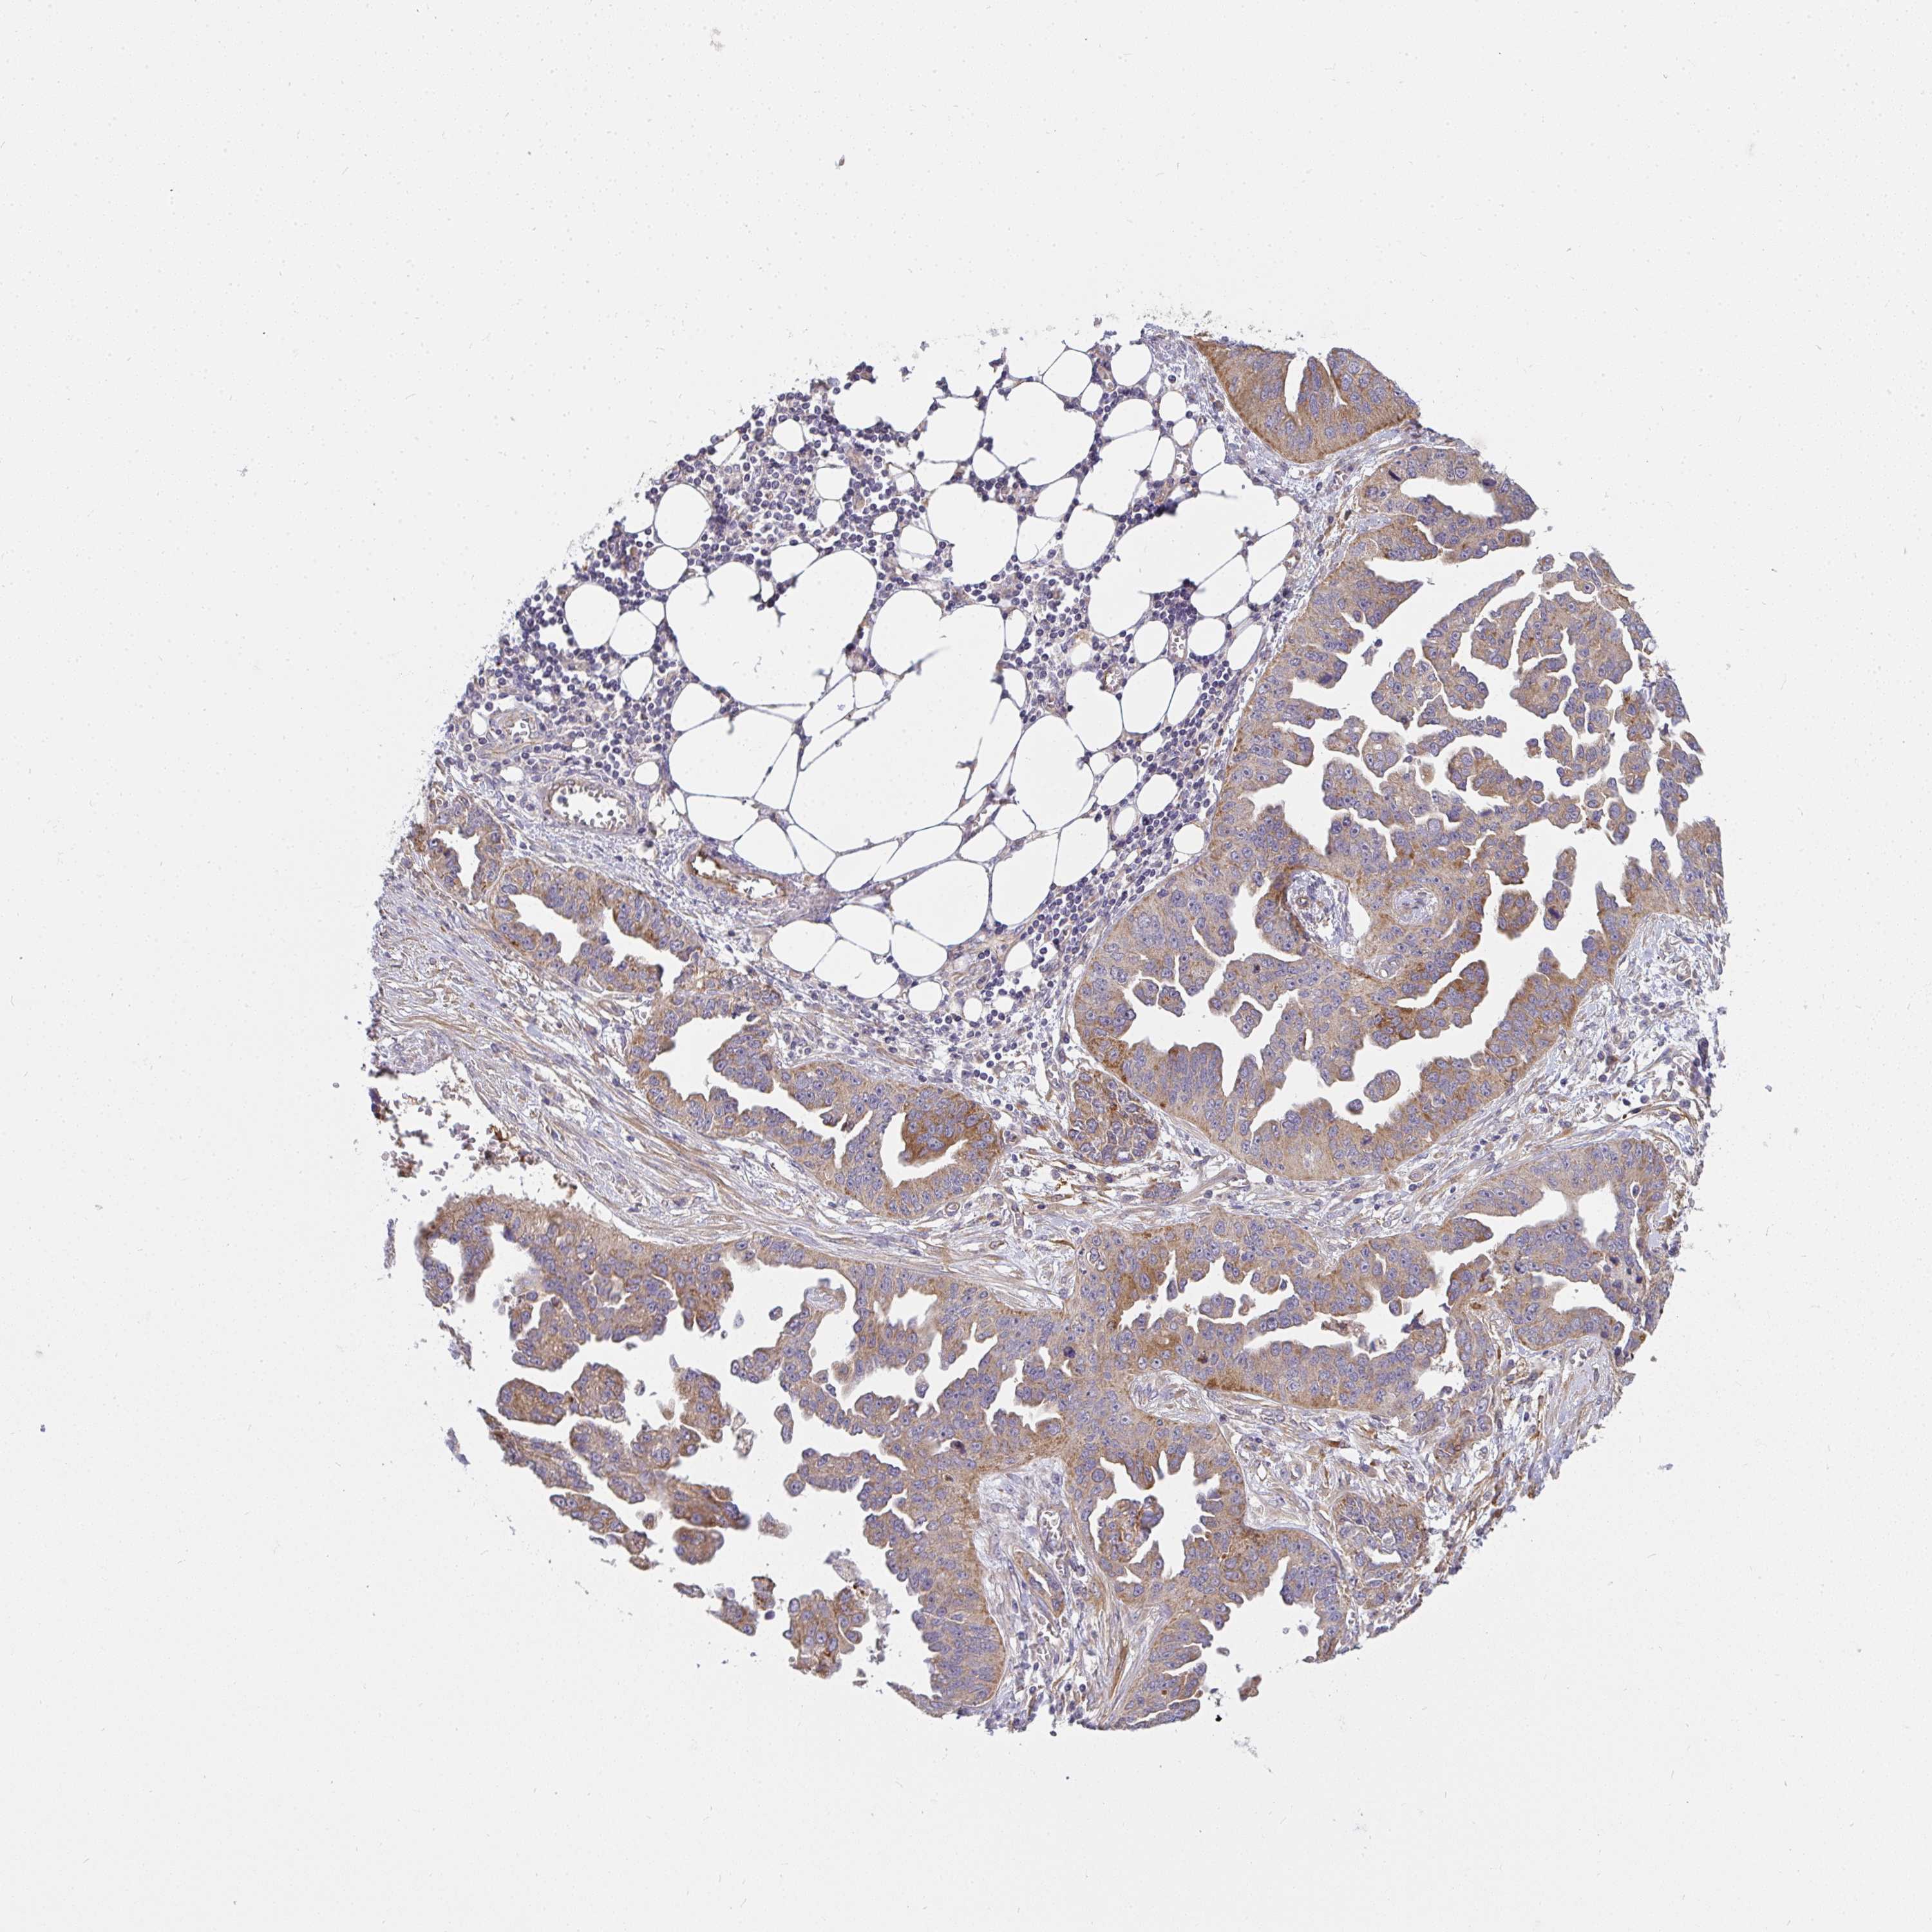

OVARIAN CANCER - Protein expressioni

A mouse-over function shows sample information and annotation data. Click on an image to view it in a full screen mode. Samples can be filtered based on level of antibody staining by selecting one or several of the following categories: high, medium, low and not detected. The assay and annotation is described here.

Note that samples used for immunohistochemistry by the Human Protein Atlas do not correspond to samples in the TCGA dataset.

Antibody stainingi

Antibody staining in the annotated cell types in the current human tissue is reported as not detected, low, medium, or high, based on conventional immunohistochemistry profiling in selected tissues. This score is based on the combination of the staining intensity and fraction of stained cells.

Each image is clickable and will lead to virtual microscopy that enables deeper exploration of all samples and also displays staining intensity scores, fraction scores and subcellular localization as well as patient and tissue information for each sample.

Antibody HPA058284

Antibody CAB020701

Staining

High

Medium

Low

Not detected

Intensity

Strong

Moderate

Weak

Negative

Quantity

>75%

75%-25%

<25%

None

Location

Nuclear

Cytoplasmic/membranous

Cytoplasmic/membranous,nuclear

Carcinoma, endometroid